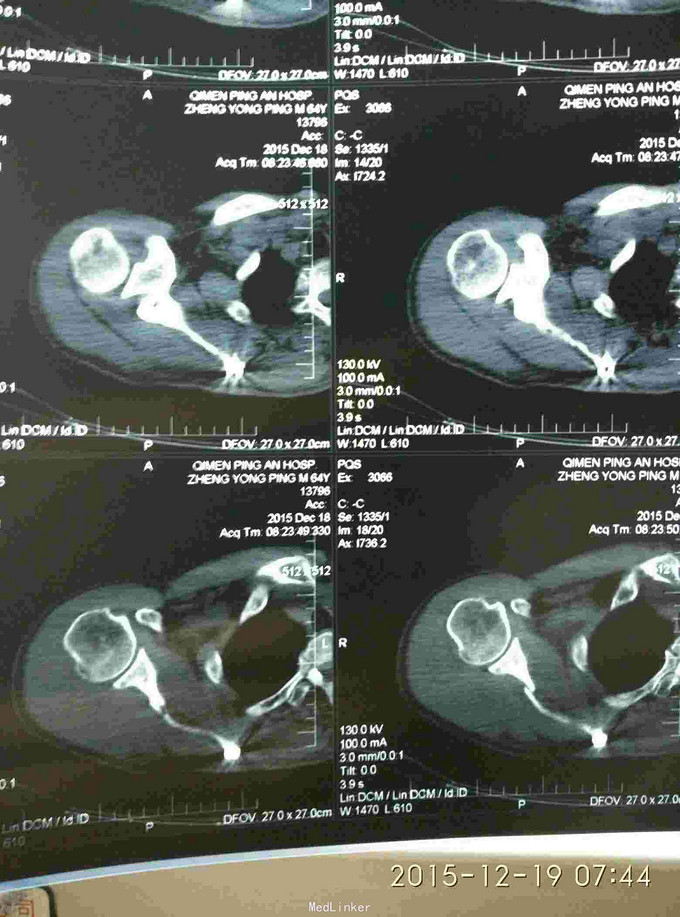

右肩峰及肩胛骨骨折

骨折 肩峰骨折 肩胛骨骨折

胸廓挤压试验阳性,右肩峰压痛阳性,右肩主动活动受限,外展约30度。x片及CT示右肩峰骨折及肩胛骨骨折,右第6.7.8.9肋骨骨折。

右肩峰骨折,右肩胛骨骨折,右第6.7.8.9肋骨骨折

是保守还是手术?